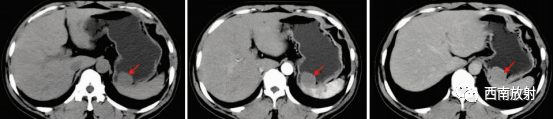

▲间质瘤:女,73 岁,查体发现右上腹软组织肿块。CT平扫见胃窦部向腔内外生长软组织肿块影,大小130 mm×67 mm,其内见多发低密度影及点片状钙化影(箭头);动脉期呈不均匀明显强化,并见强化血管影(箭头)。平衡期呈持续性强化,内低密度影未见强化[4]。